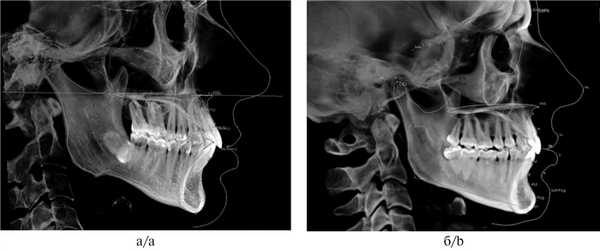

Два сканирования челюстно-лицевой области, время — по 23 с, высота FOV — 8,5 см, диаметр — 14 см, сшивка (stitching), размер воксела — 0,25. Позиционирование головы — естественное (natural head position), в привычной окклюзии. Автоматическое репозиционирование рендеринга при проведении программного 3D-цефалометрического анализа. Проводили двумерные измерения 3D исследуемого объекта. Анализ данных КЛКТ у пациентов с краниомандибулярной дисфункцией, применяемый в нашей практике, разделен на несколько блоков.

I. Оценка пропорций скелета

1. Оценка развития премаксиллярной зоны верхней челюсти (цефалометрический анализ по Sassouni PLUS). Для измерения премаксиллярной зоны верхней челюсти необходимо построить плоскость твердого неба, проведя линию из точки ANS (передняя носовая ость) к точке PNS (задняя носовая ость), а также продольную ось верхнего центрального резца — U1. Данная ось делит верхнюю челюсть на premaxilla (передняя часть верхней челюсти) и дистальную часть верхней челюсти. В норме длина премаксиллярной области (расстояние от ANS до пересечения оси верхнего резца и небной плоскости) составляет 12—15 мм. Расстояние менее 12 мм свидетельствует о недоразвитии верхней челюсти, а именно передней ее части (рис. 1, а).

Рис. 1. Измерения в программе InVivo 5 Anatomage.

а — премаксиллярной зоны верхней челюсти (9,53 мм); б — длины мыщелковой ветви нижней челюсти (61,32 мм).

2. Измерение длины мыщелковых отростков ветвей нижней челюсти. Для того чтобы исключить скелетную природу асимметрии, обусловленную короткой ветвью нижней челюсти, необходимо провести измерение как мыщелковых отростков челюстей, так и мыщелков. Измерение мыщелковых отростков проводят параллельно касательной заднего края ветви между наиболее верхней точкой головки нижней челюсти Co (Condylion) и точкой Go (Gonion — нижняя точка угла нижней челюсти) (рис. 1, б) [1]. Для исключения наличия кондилярной деформации (гиперплазии или аплазии мыщелка) измеряют расстояние от точки Co (Condylion) до нижней точки нижнечелюстной вырезки (incisura mandibulae).